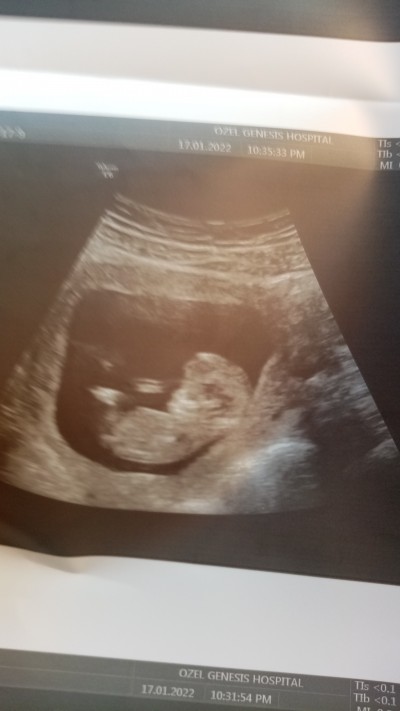

12+6 haftalık cinsiyet hamini arkadaşlar

Gebelik haftası 12+6

Kuzum.bende bu sabah hastaneye gittim 12.6 haftamdayim cinsiyetini göstermedi kiz yapisina benziyor dedi kiz ve erkek demiyorum dah cok kucuk size tahminde bulundumu ogle diyipde degise biliyormu bende ck merak ettim sizinkiniz daha net gorunuyor ultrasyonunuz

Bana cinsiyet oluşmamış dedi ama tahmini kıza benziyor dedi ama sakın pembe kıyafetler alma dedi